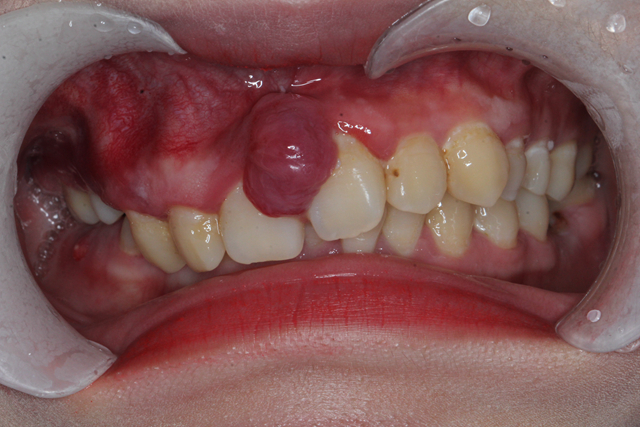

出血和牙龈萎缩还不是牙结石能够引发的严重的危害,牙结石会引发牙周脓肿。

牙结石会因为细菌产生牙龈炎症,而在在炎症长时间无法消除的情况下,造成炎症范围逐渐扩大,并且会产生脓液。脓液因为被牙龈和牙结石包裹无法排出,所以渗出物会在里面越积越多,从而形成脓肿。在不采取治疗措施的状况下,脓液会慢慢侵蚀牙齿根部,导致牙齿松动,造成牙齿脱落。